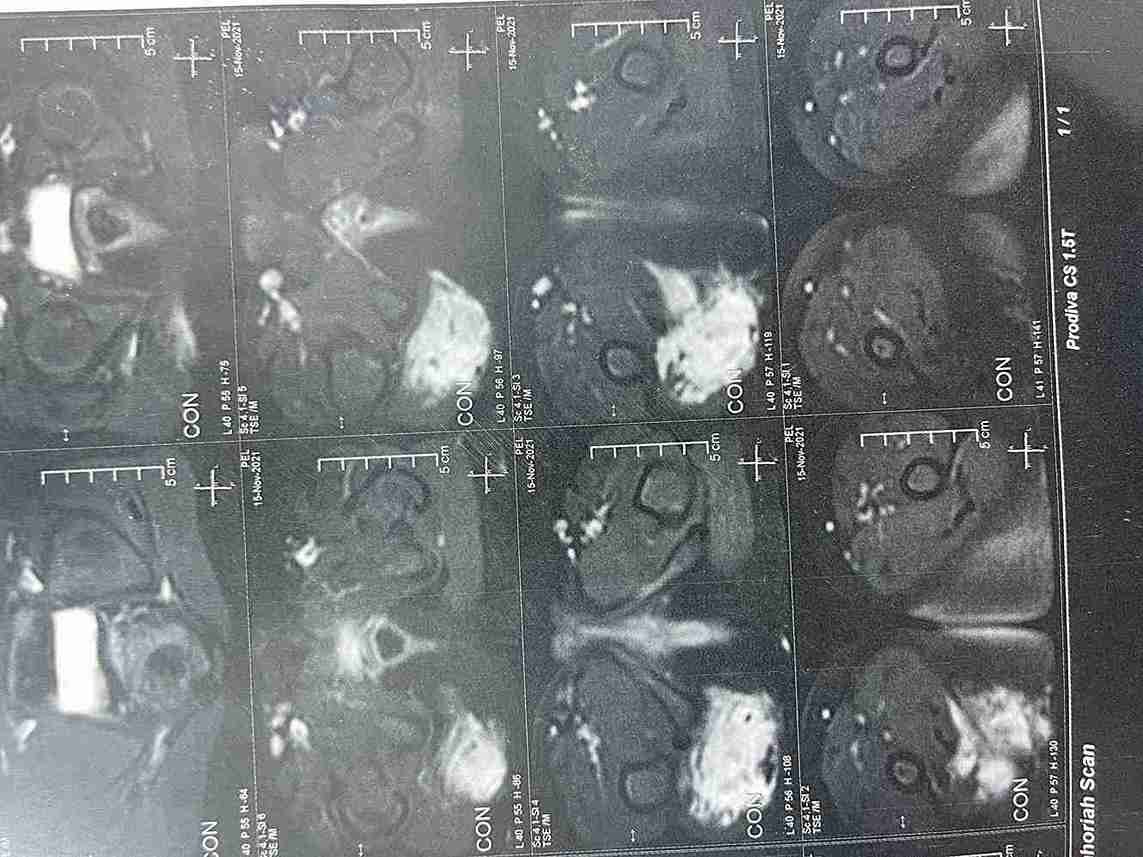

ورم بغلاف عصب عرق النسا الايمن بطفلة خمس سنوات ونصف

tumor in the right sciatic nerve in a five-and-a-half-year-old girl

Surgery for a Schwannoma on the Sciatic Nerve in a Child

This case involved the successful removal of a rare, benign tumor from the sheath of the right sciatic nerve in a 5.5-year-old girl. The tumor was causing pain in the thigh and buttock area. The surgery was performed with complete success, fully preserving the nerve's function.